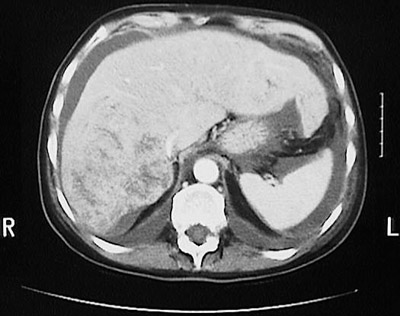

This abdominal CT scan in axial view demonstrates a large mass that occupies most of the posterior right lobe of the liver. This is an hepatocellular carcinoma. These cancers can appear as one large mass, or there may be small surrounding satellite nodules, or multifocal masses. The serum alpha-fetoprotein (AFP) is often elevated with hepatocellular carcinoma.